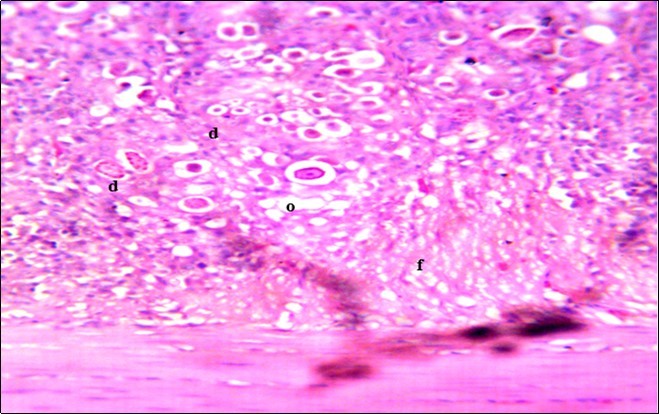

Figure 4.Photomicrograph of caecum of chick administered 20000 Oocysts of Eimeria tenella and untreated showing generalized degeneration of the caecal glands (d) with massive Ocysts (o) and gametocytes (g) largely within the caecal glands X250 (H&E).

In this study, the reduction in oocyst count observed in the treated group was compared with amprolium could be attributed to the presence of a bioactive compounds azadiractin A which is known to bind membrane cholesterol, altering the integrity of the parasite membrane, resulting in loss of homeostasis and eventual death of the parasite 29]. Also, limonoids contained in NeemAzal® inhibit protein digestion and uptake of vitamins and minerals by the parasites in the gut 17. This action results in impaired nutrient utilization, reduced growth, and multiplication of the parasite which could contribute to the reduced oocyst count observed. Extracts of neem and mahogany when used individually have been reported to reduce oocyst count in avian coccidiosis 11,12. The observed reduction in oocyst count and the significant increase in weight gain of the birds when treated with NeemAzal®, as compared with the negative control group could probably be due to the inhibition of inflammation in the intestinal mucosa which is suggestive of an increased nutrient absorption across the intestinal wall and enhanced feed conversion ratio compared to the negative control this is in agreement with reports by Nwosu et al.12 and Biu et al.11 who also reported an increased weight gain and feed conversion ratio in birds treated with only Khaya senegalensis extracts and Azardiractaindica, respectively. The observed increase in RBC and haemoglobin concentration is indicative of the erythropoieticability of the NeemAzal®, which is beneficial since the Eimeria parasite in the epithelia of the intestines causes bloody diarrhoea and consequently anaemia (Table 1). This finding is in consonance with 15 who reported an anti-anaemic effect of Khaya Senegalensis on phenyl hydrazine-induced anaemia in rats. Neem has been shown to possess anti-anaemic properties in rats 14. The significant increase in mean weight gain in treated birds when compared to the negative control is possibly due to the inhibition of inflammation in the intestinal mucosa which is suggestive of an increased nutrient absorption across the intestinal wall and enhanced feed conversion ratio compared to the negative control. Nwosu et al.12 and Biu et al.11 reported an increased weight gain and feed conversion ratio in birds treated with only Khaya Senegalensis andAzadiractaindica extracts, respectively. In a similar study, Neem acts like toltrazuril exhibiting anticoccidial. In addition, exposure of broiler chickens to 20000 Oocysts of Eimeria tenellacaused generalized degeneration of the caecal glands with massive Oocysts and gametocyts within the caecal glands with fibrosis (Figure 3, Figure 4 & Figure 5), however, broiler chickens treated with NeemAzal® post exposure to 20000 Oocysts of Eimeria tenella, shows equal numbers of caecal tissues with non-observable histopathological lesions (Figure 4), possibly due to the antioxidant and anti-coccidian effects of NeemAzal®. The exact mechanism of action of neem against coccidian parasites is unknown, but a report by the National Research Council 1992 30, suggested that aqueous neem leaf extract, when taken orally, produces an increase in red cells, white blood cells and lymphocyte counts thus enhancing the cellular immune response, increasing antibody production and so most pathogens can be removed before they cause the symptoms associated with disease this was in agreement with this study as seen in Table a remarkable increase of the RBCs.